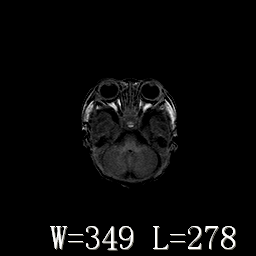

脑干形态欠规则,信号增高,不知怎么解释?

脑干背侧面t1高信号是,新生儿正常已经髓鞘化好的部位